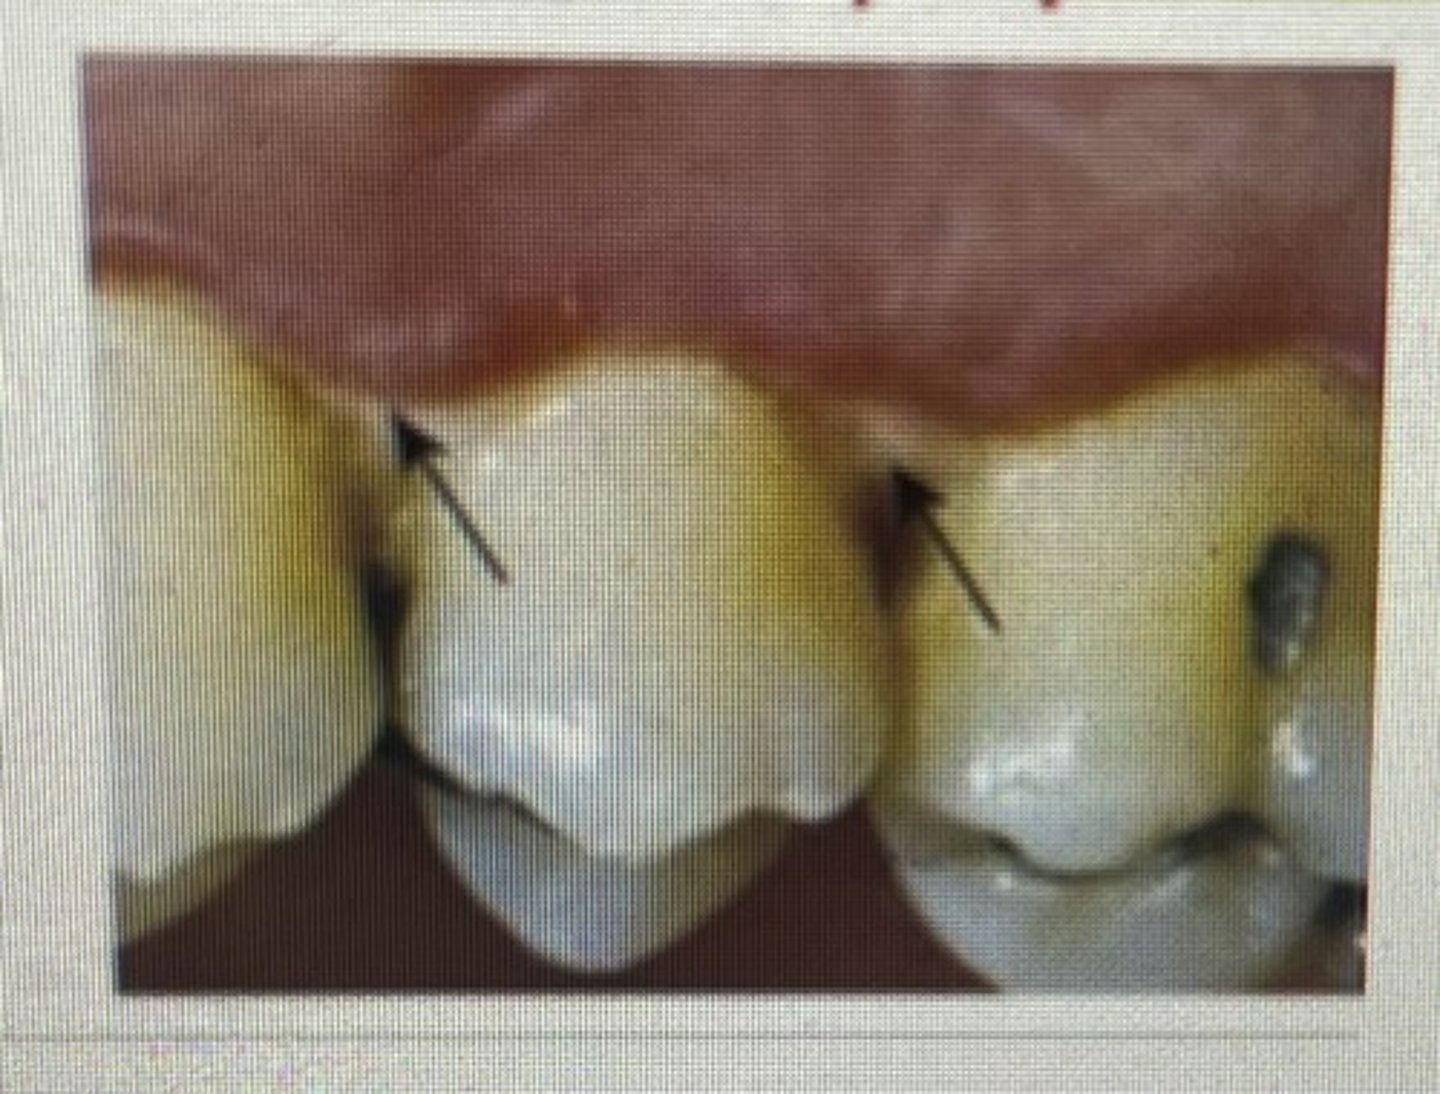

class II blacks

proximal surfaces of posterior teeth